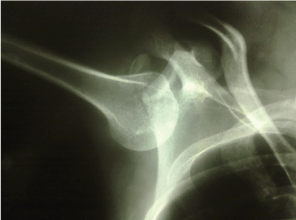

The X-ray findings showed the humeral shaft pointed up, in a rotated position, with the dislocated humeral head below the glenoid fossa associated with greater tuberosity fracture (Figure 2). Manipulative reduction by traction-counter-traction was performed immediately under general anesthesia. Counter-traction was applied with a rolled bed sheet placed superior to the shoulder. The radiographic views, checked immediately after close reduction, revealed anatomic reduction of the humeral head into the glenoid fossa and reduction of the greater tuberosity fracture (Figure 3).

Figure 2: Antero-posterior X-ray view of the right shoulder: Inferior dislocation associated with a fracture of the greater tuberosity. View Figure 2